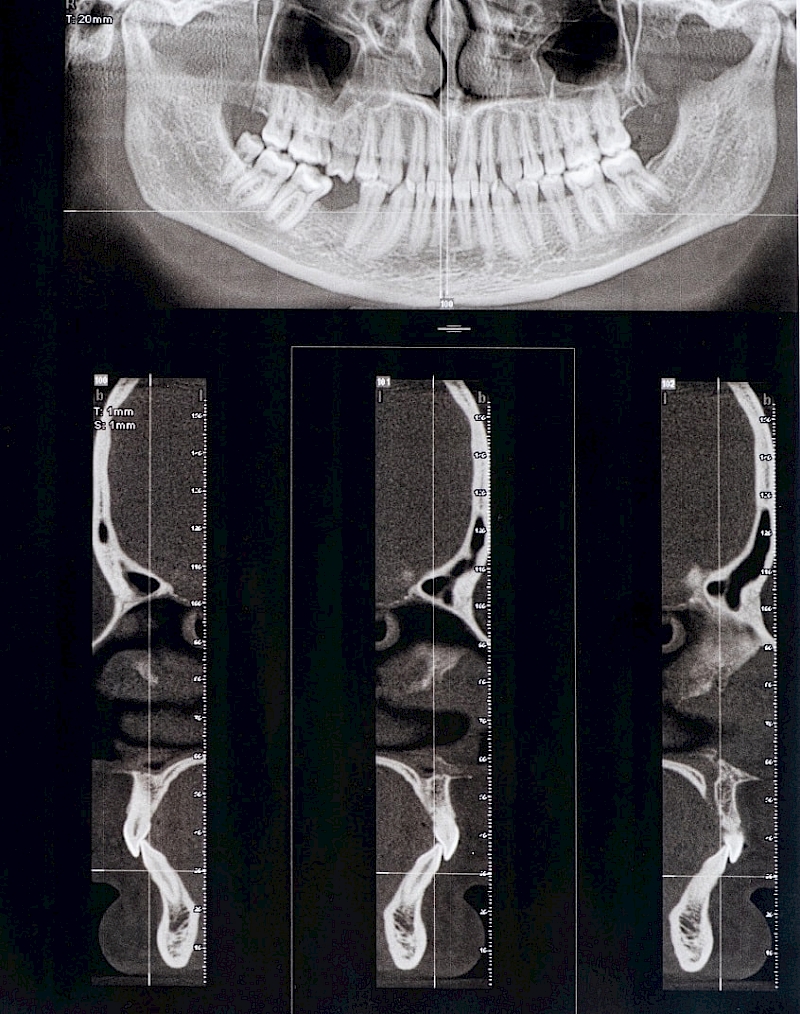

Methods by which you can check your jaw joint

Put your fingers in your ears, open and close your mouth several times. Do you feel clicking sounds?

Stand in front of the mirror and slowly open and close your mouth. Is there a shift to the other side or pain when opening?

Slide your jaw from one side to the other and note if there is pain.

Check the Sensitivity of Your Muscles

Place your fingers on the area where your joints are, which are slightly in front of your ears, apply pressure to your cheek area.

If you feel any discomfort or pain in your jaw joint, consult a dentist who specializes in TMJ.